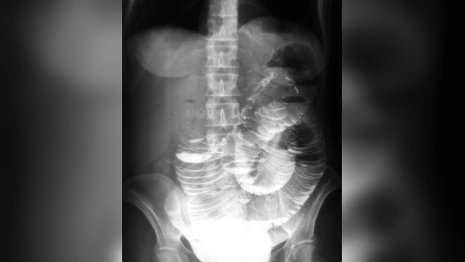

Подросток поступил в больницу с жалобами на сильные боли в животе, многократную рвоту и вялость. Девочку госпитализировали с подозрением на кишечную непроходимость.

Пациенту провели срочную операцию. Врачи выявили два многоцилиндровых инвагината. Им удалось провести расправление.

В составе одного из них обнаружили опухоль размерами 5 на 5 на 5 см. Ее удалили. Сейчас девочку выписали.

Инвагинация кишечника – это внедрение одной части кишки в другую, в результате которого развивается кишечная непроходимость. Чаще инвагинация кишечника встречается в возрасте от 4 до 9 месяцев (85 – 90% случаев). Мальчики страдают в два раза чаще девочек.